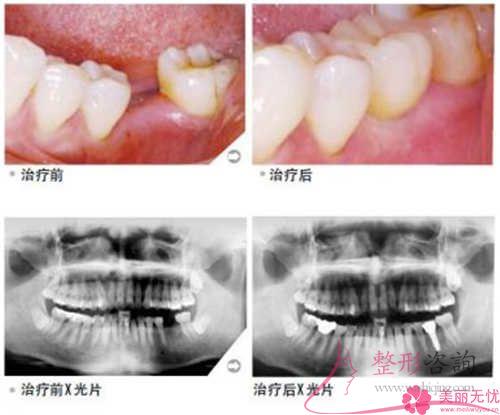

通俗地說,種植牙即是依照外科手術(shù)的法子,將人工種植牙材料打造的種植牙的移植體移植缺牙區(qū)域的牙槽骨頭中,當(dāng)成牙根,然后以此作為基礎(chǔ)還原缺少的牙齒。